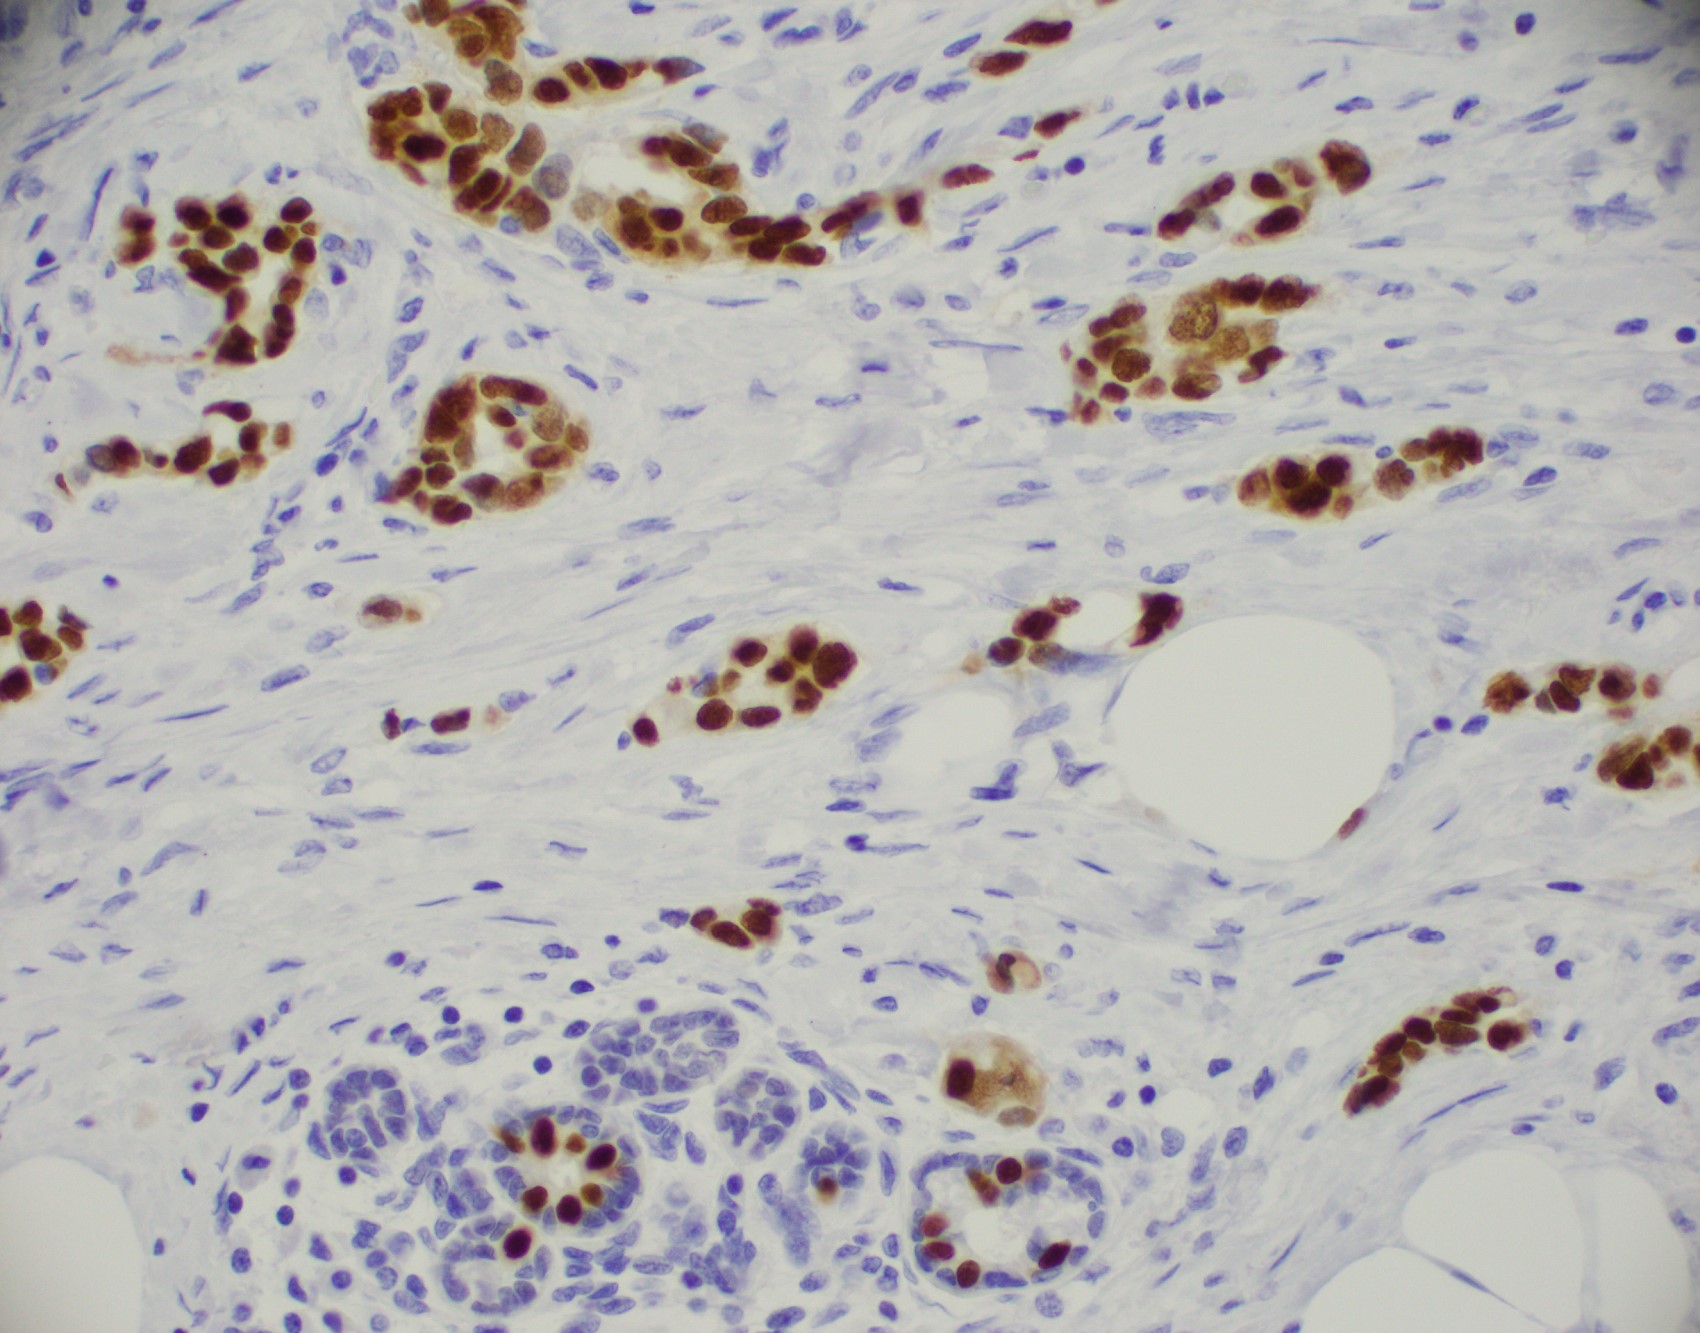

Microscopic (histologic) images

Contributed by Julie M. Jorns, M.D., Kristen E. Muller, D.O., Gary Tozbikian, M.D. and Emad Rakha, M.D.

Positive stains

- Luminal low molecular weight cytokeratins (CK8 / 18, CK19 and CK7 and pancytokeratins such as AE1 / AE3, CAM 5.2, MNF-116), EMA, E-cadherin, p120, ER (60 - 80%), PR (50 - 70%), HER2 (15 - 20%) (Am J Clin Pathol 2006;125:377)

- GATA3 (~91 - 100% of hormone receptor positive breast cancers, ~43 - 66% in triple negative breast cancer) (Hum Pathol 2014;45:2225, Hum Pathol 2015;46:1829)